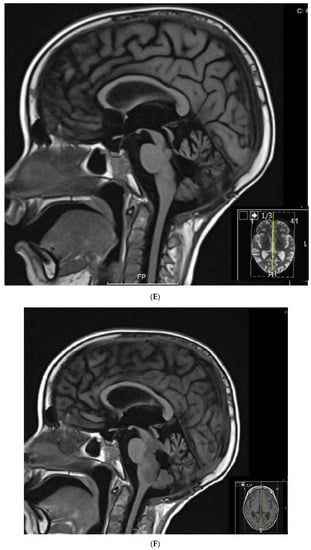

1.2. Patient 2

Patient 2 was diagnosed with anaplastic ependymoma when he presented with right hemianopsia, severe vision loss, and a 12 cm × 8 cm × 8 cm left temporo-occipital tumor at 6 years of life. He had two consecutive surgeries to remove the tumor, but a 1 cm unresectable lesion was left behind. He then received 5940 cGy field radiation to the tumor bed. Three months after radiation, he developed seizures, transient right arm paralysis, and recurrent disease to the left cerebral hemisphere, for which he received vincristine, carboplatin, and cyclophosphamide following the guidelines of ACNS0121 [35]. Three months later, he developed progressive disease with a large infiltrative enhancing mass (~5 cm) in the left temporal, occipital, and parietal lobes with involvement of the left thalamus, internal capsule, left external capsule, and insula, as well as leptomeningeal metastasis to the thoracic spine. He had no access to Phase I or II studies and was unable to travel for lack of insurance and migratory status, for which treatment was changed to palliation chemotherapy with oral VP16 (50 mg/m2/day for 21 days) alternating with oral CTX (50 mg/m2/day for 21 days) and continuous celecoxib (120 mg/m2 PO bid) and VA. Celecoxib was subsequently changed to sulindac (8 mg/kg/day) due to drug access issues. He had an excellent response to palliation with resolution of all enhancing lesions and no evidence of residual disease after 2 years of therapy. (Figure 2). About this time VA was added to his seizure disorder management and continued until his last visit. He received 18 additional months of metronomic chemotherapy after complete response. He had no evidence of recurrent disease when he was lost to follow up 8 years from initial diagnosis and 4 years off metronomic chemotherapy. This patient showed complete response to the metronomic regimen.

Figure 2.

Patient 2: MRI shows confluent encephalomalacia gliosis in the left temporal and occipital lobes. There was no evidence of mass or pathologic enhancement 8 years from diagnosis and 4 years off therapy.